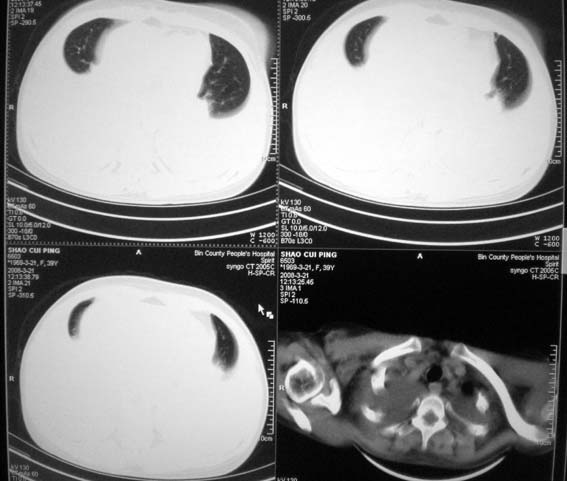

以下是引用随光逐影在2008-3-21 23:13:00的发言:[br]1)右肺中叶及左肺上叶舌段感染性病变。2)右肺中叶周围型肺癌待排。3)双侧胸腔积液并双下肺部分肺组织膨胀不全。4)心包积液。

以下是引用拾荒者在2008-3-22 21:21:00的发言:[br]胸腔积液、心包积液,双下肺膨胀不全,建议穿刺细胞学检查或抽液后进一步ct检查。